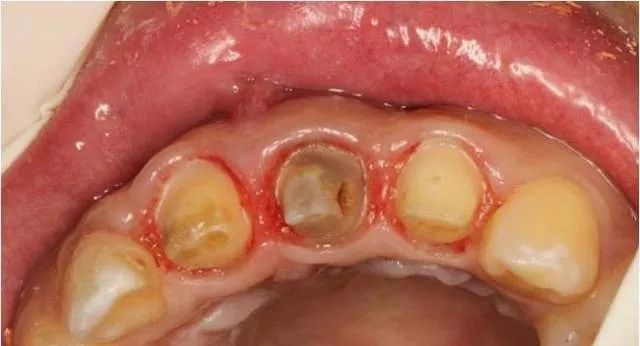

局麻下翻瓣

术中

翻瓣后清除炎性组织

颈缘骨修整

软组织修复整

间断缝合